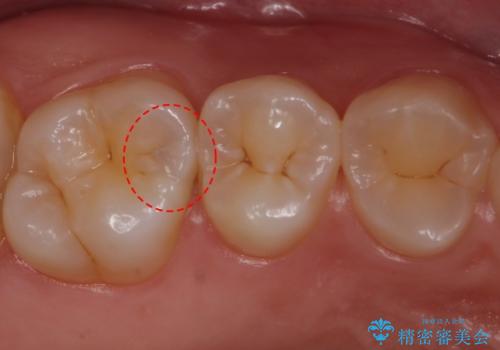

- 全体的にむし歯を治していきたいとのことで来院。

検査の結果、症状はないものの右上の奥歯に虫歯が見つかりました。

笑うと外からも見える位置であるため、白いセラミックでの治療となりました。

局所的に深い虫歯が確認されましたが、神経は温存することができました。

歯と歯の間から広がる虫歯は目視では確認しにくいため、定期的にチェックし悪化を予防することが大事です。